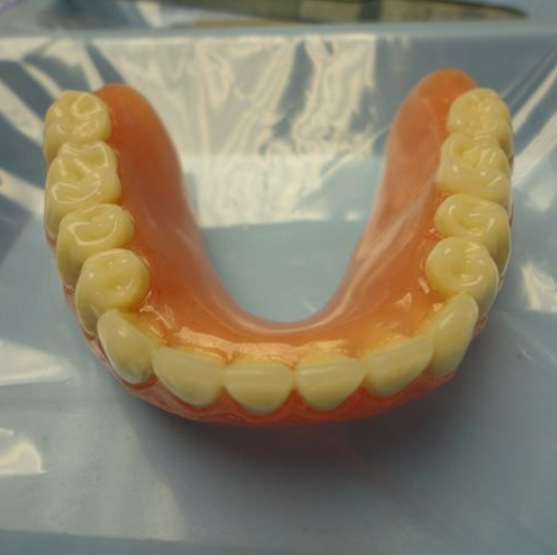

Snap-in Dentures

Over-Dentures with Implant Precision Attachments (Lower)

Snapped in and ready to go!